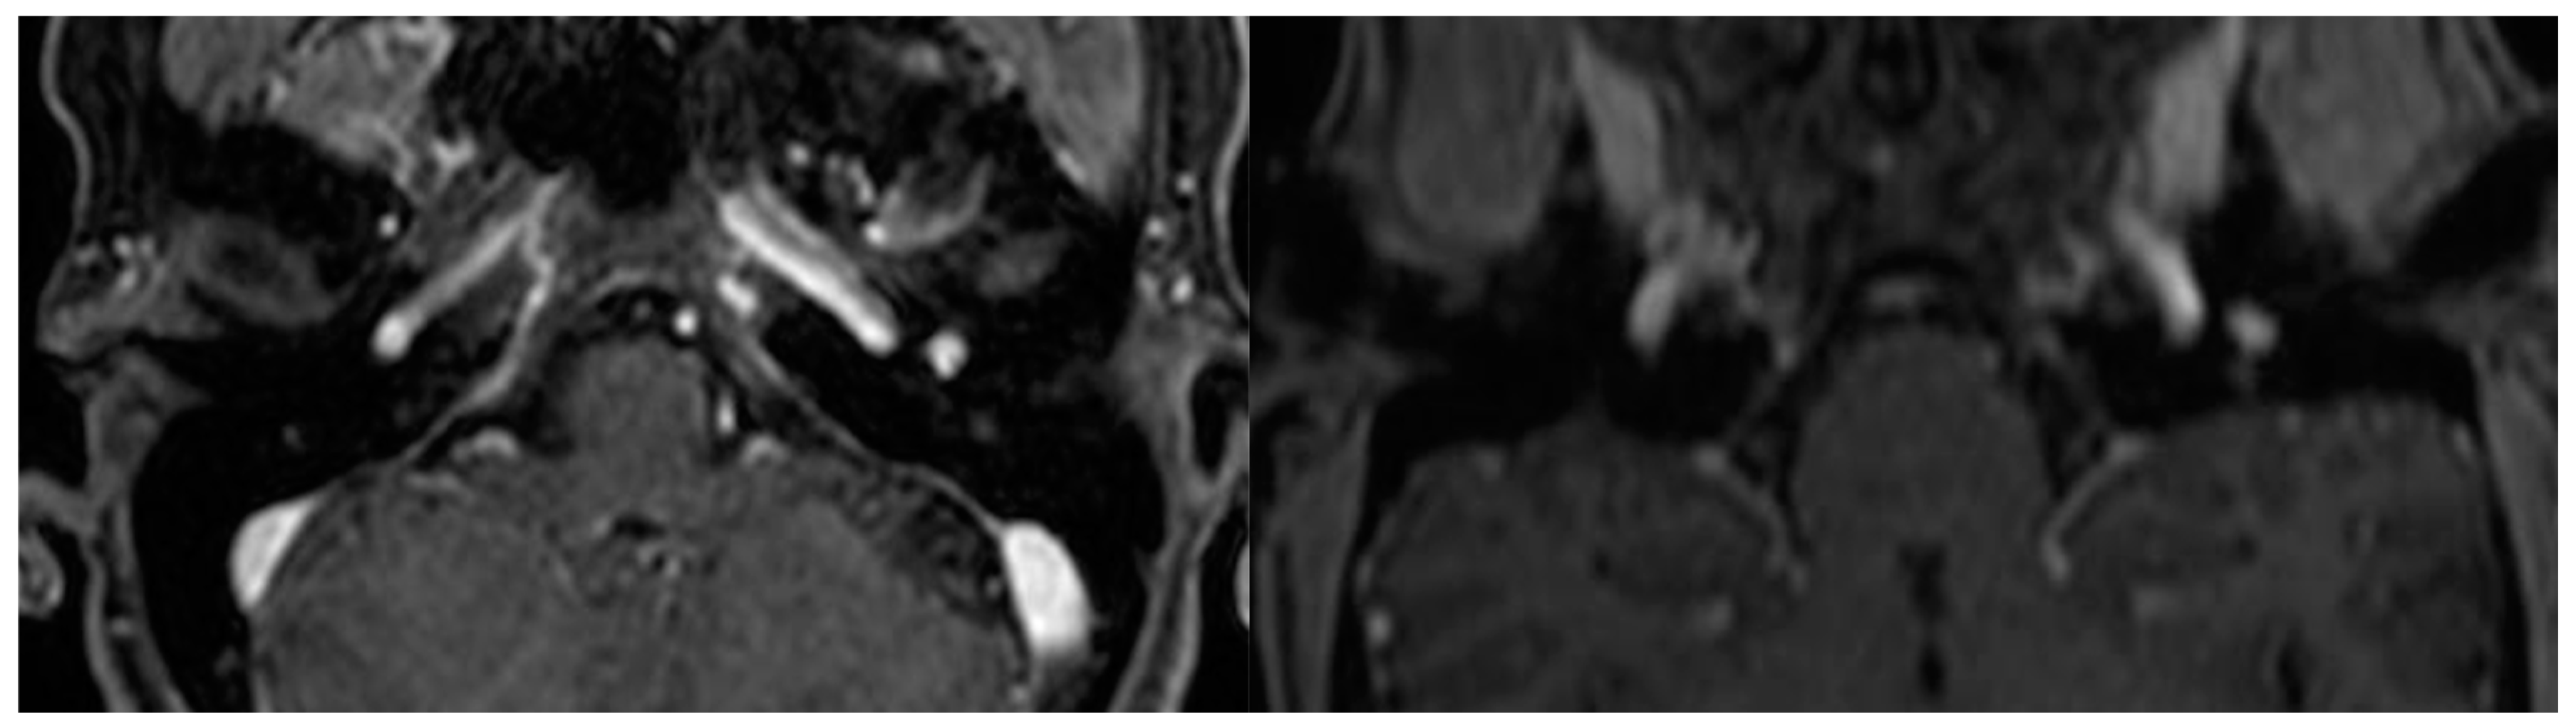

| A | Tumors limited to the middle ear cleft |

| B | Tumors limited to tympanomastoid compartment of the temporal bone |

| B | Tumors limited to the tympanomastoid compartment of the temporal bone |

| B1 | Tumor filling the middle ear cleft with extension into the hypotympanum and tympanic sinus |

| B2 | Tumor filling the middle ear cleft, extending into the mastoid and medially to the mastoid segment of the facial nerve |

| B3 | Tumor filling the middle ear cleft, extending into the mastoid with erosion of carotid canal |